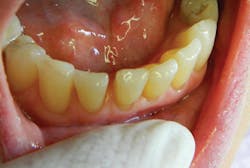

The noncontact technique enables restoration of delicate areas, such as worn incisal edges of lower anteriors, which often absorb stain over time and cause cosmetic concerns for many patients. The lack of collateral damage when using a laser (unlike the microfractures created by the vibration of a drill), and the ability to create convergence toward the incisal simply by changing angulation of the laser tip from buccal to lingual, provide both macro- and microretention, and hence, the longevity of these restorations (figures 5a and 5b).

Figures 5a and 5b: Class VI anterior incisal attrition restoration